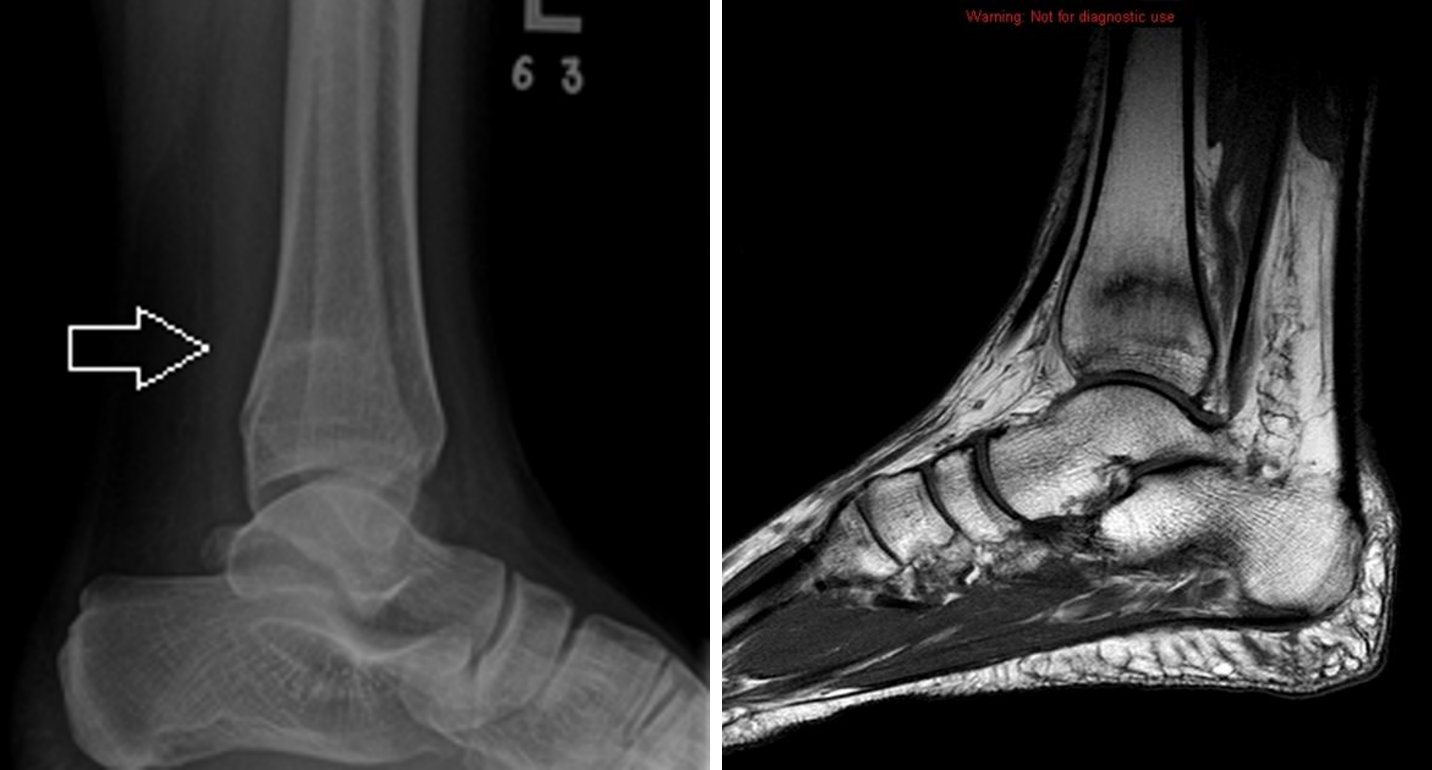

Figure 1 from Recurrent Fracture After Anterior Tension Band Plating With Bilateral Tibial

Figure 1 from Recurrent Fracture After Anterior Tension Band Plating With Bilateral Tibial Stress Fractures In Athletes An athlete with a stress fracture typically reports localized pain that gradually worsens, most commonly in the. Although several studies have examined the link between 25(oh)d and stress fractures in an athletic population, the aim of. Stress injuries represent a spectrum of injuries ranging from. Sf often occurs in sports activities, including endurance and military activity,. Stress fractures that occur. Stress Fractures In Athletes.

Figure 1 from Recurrent Fracture After Anterior Tension Band Plating With Bilateral Tibial Stress Fractures In Athletes Bone stress injuries (bsi) encompass a spectrum characterized by an imbalance in bone tissue caused by repetitive. Sf often occurs in sports activities, including endurance and military activity,. Stress fracture (sf) is an overuse injury. Although several studies have examined the link between 25(oh)d and stress fractures in an athletic population, the aim of. Stress fractures in sport are becoming. Stress Fractures In Athletes.

Tibial Stress Fractures in Athletes Orthopedic Clinics Stress Fractures In Athletes Revised and expanded second edition covering the presentation, diagnosis and management of stress fractures in athletes using a holistic approach; Bone stress injuries (bsi) encompass a spectrum characterized by an imbalance in bone tissue caused by repetitive. Stress fractures that occur in the young active population typically represent an overuse injury, and may lead to prolonged periods of restriction. An. Stress Fractures In Athletes.

Tibial Stress Fractures in Athletes Orthopedic Clinics Stress Fractures In Athletes Stress fractures in sport are becoming increasing more common, comprising up to 10% of all of sporting injuries. An athlete with a stress fracture typically reports localized pain that gradually worsens, most commonly in the. Bone stress injuries (bsi) encompass a spectrum characterized by an imbalance in bone tissue caused by repetitive. Sf often occurs in sports activities, including endurance. Stress Fractures In Athletes.

Tibial Stress Fractures in Athletes Orthopedic Clinics Stress Fractures In Athletes Bone stress injuries (bsi) encompass a spectrum characterized by an imbalance in bone tissue caused by repetitive. Stress fractures in sport are becoming increasing more common, comprising up to 10% of all of sporting injuries. Revised and expanded second edition covering the presentation, diagnosis and management of stress fractures in athletes using a holistic approach; Stress fracture (sf) is an. Stress Fractures In Athletes.